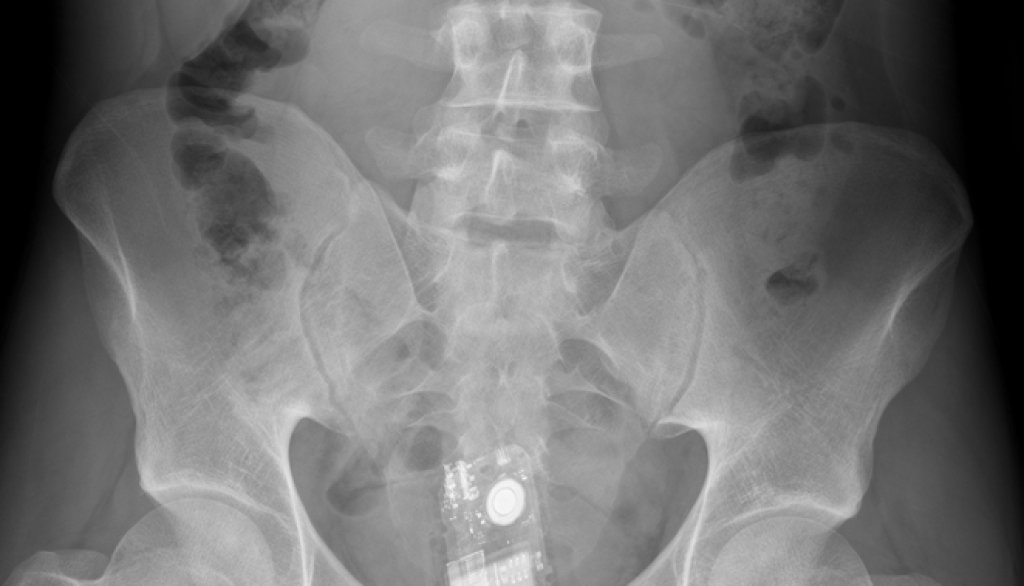

Е, той не може, но тези снимки говорят сами за себе си. И за хората, чиито са. Хора с (меко казано) доста извратени сексуални фантазии.

Тези осем примера показват това, което рентгенът не може да каже и затова докторите го правят вместо него. Вижте ги в галерията.